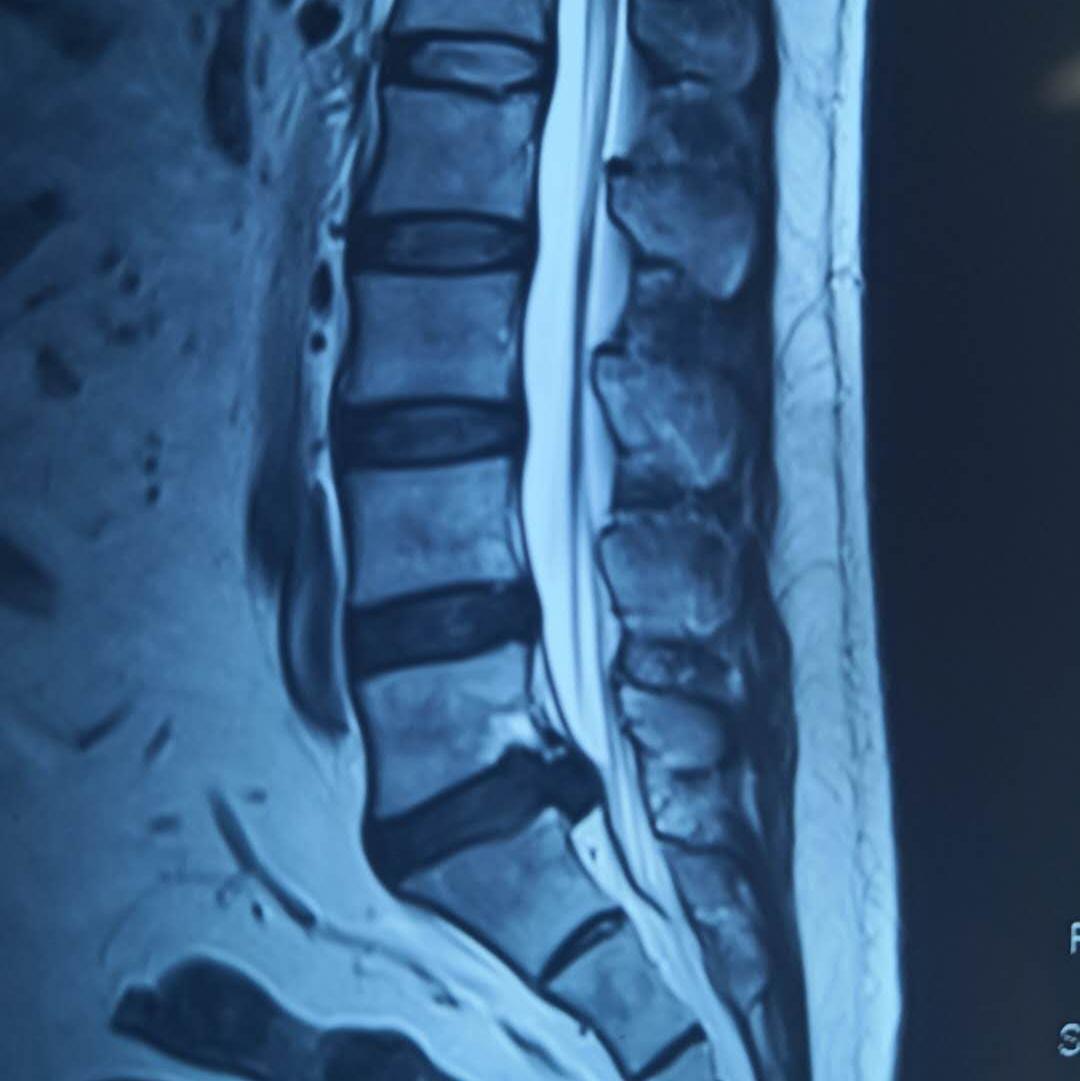

近日,陕西中医药大学第二附属医院(西咸新区中心医院)推拿疼痛科病区收治了一位年仅35岁的青年男性患者,腰痛伴右下肢放射痛5年,加重3天。VAS疼痛评分为8-9分,疼痛难以入眠,无法站立、行走。经医生查体,该患者腰3-骶1棘间及双棘旁压痛(+),叩击痛(+),直腿抬高试验70/45,右侧跟腱反射较对侧减弱,跖屈乏力。腰椎MRI结果显示,腰5-骶1椎间盘脱出。经综合考虑,该患者被诊断为腰椎间盘突出症。